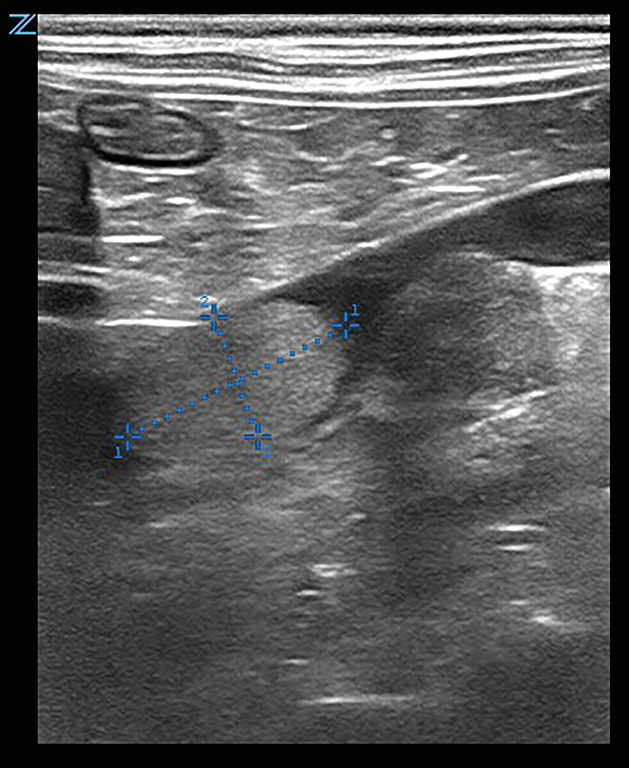

En el abdomen la glándula adrenal derecha presenta pérdida de estructura y una anchura de 17 mm; comprime la vena cava caudal, que presenta un trombo (imágenes 4 y 5). Estos hallazgos sugieren cardiomiopatía hipertrófica secundaria a hipertensión arterial sistémica y neoplasia adrenal derecha con trombosis venosa.

Imágenes ecográficas de la glándula adrenal derecha aumentada de tamaño, con pérdida de forma normal y estructura intravascular hiperecogénica adherida a vena cava caudal, compatibles con neoplasia adrenal y trombo en dicha vena.